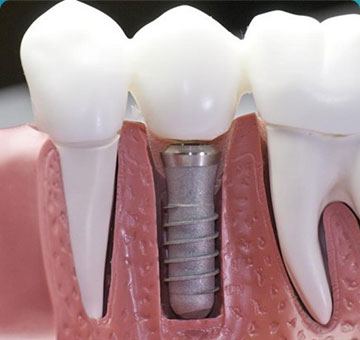

1 通过高智能数字化检查系统扫描得到口腔精准数据,同时兼顾后期修复等诸多因素进行综合考虑,量“齿”定制一种顶级高难度治疗方案——穿颧种植,帮助张阿姨恢复一口好牙! 01 什么是穿颧种植? ![]() 穿颧种植:穿颧种植被称为是当今难度较高的种植技术,指的是颧骨固定种植技术,该技术无论稳定性还是受力性都非常好,也是当今难度较高的种植技术。适用于上颌骨切除、上颌骨重度萎缩、常规内外提升都没有办法达到种植条件的无牙颌患者,通俗地被人称为“无土培栽技术”。 02 为什么说“穿颧种植” 是种植界的“珠穆朗玛峰”? 穿颧手术的关键还是在于患者剩余骨量比较少,需要做一个比较长的颧种植体,植入颧骨区。因为患者牙槽骨严重萎缩,暴露口腔颌骨区域比较少,需要医生对解剖结构比较了解,才能在有限的视野里面成功植入一个比较长的颧种植体。因此,对医生术前设计和术中的操作以及临床经验是一个比较大的考验。 03 穿颧种植和常规种植相比效果如何? 穿颧种植由来已久,国外已经开展多年。综合来看穿颧种植与常规半口全口种植远期的成功率是没有根本区别的,可能只是选择的骨头位置不太一样。在国际上来看,穿颧种植10年里面的成功率大概在97%左右。 1、感觉更舒适,更自然,坚固耐用 2、具有很好的固位效果 3、使咀嚼效率达到与自然牙媲美的程度 4、刺激骨组织,延缓颌骨的吸收与萎缩 5、不损伤邻牙,并且能有效地保护邻牙 ![]() 数字化种植牙技术是将计算机断层扫描技术(CT)、计算机辅助设计技术(CAD)和快速原型制造技术(RP)综合应用于种植手术的放心、准确的方法。 |